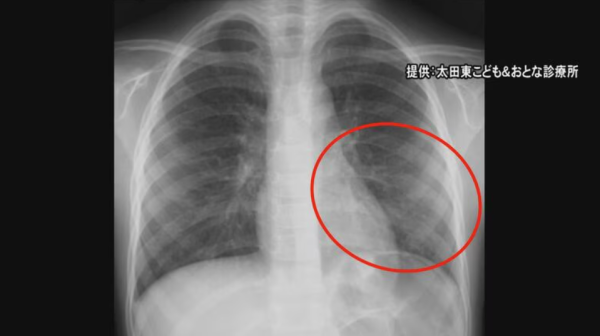

日本爆發「黴漿菌肺炎」!連續6週增感染者多兒童

近期,日本全國爆發了肺炎黴漿菌(Mycoplasma pneumoniae)疫情,這一情況引起了熱愛遊日的港人廣泛關注。黴漿菌肺炎正在日本各地肆虐,許多患者是14歲以下的兒童。日本電視台8月21日報導,黴漿菌肺炎患者數量連續6週增加,達8年來最高水平,名古屋最近亦不少出現類似症狀的兒童。

▼黴漿菌肺炎病症▼